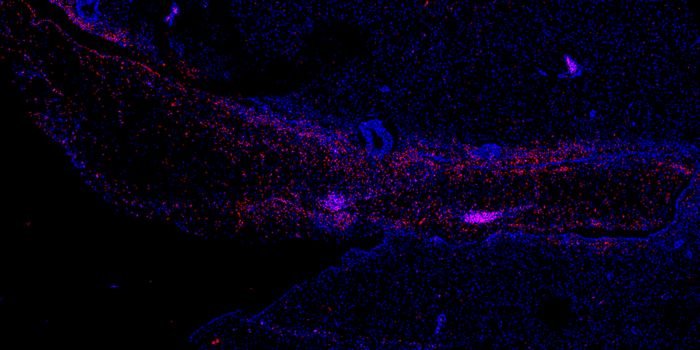

MAY 14, 2021MicrobiologyResearchers have created an imaging agent that will allow scientists and clinicians to visualize a bacterial infection c ...